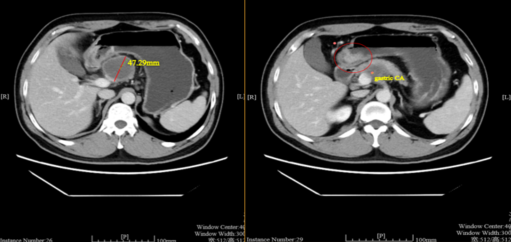

治疗3周期后(2021年11月3日):复查CT示靶病灶淋巴结缩小至29.9mm,缩小37%,疗效评估为部分缓解(PR)。

e51f106d-3b8c-421b-a587-6b609a7a1db6.png

治疗前对比治疗3周期后疗效评估

925.4.png

新辅助治疗前后胃镜结果